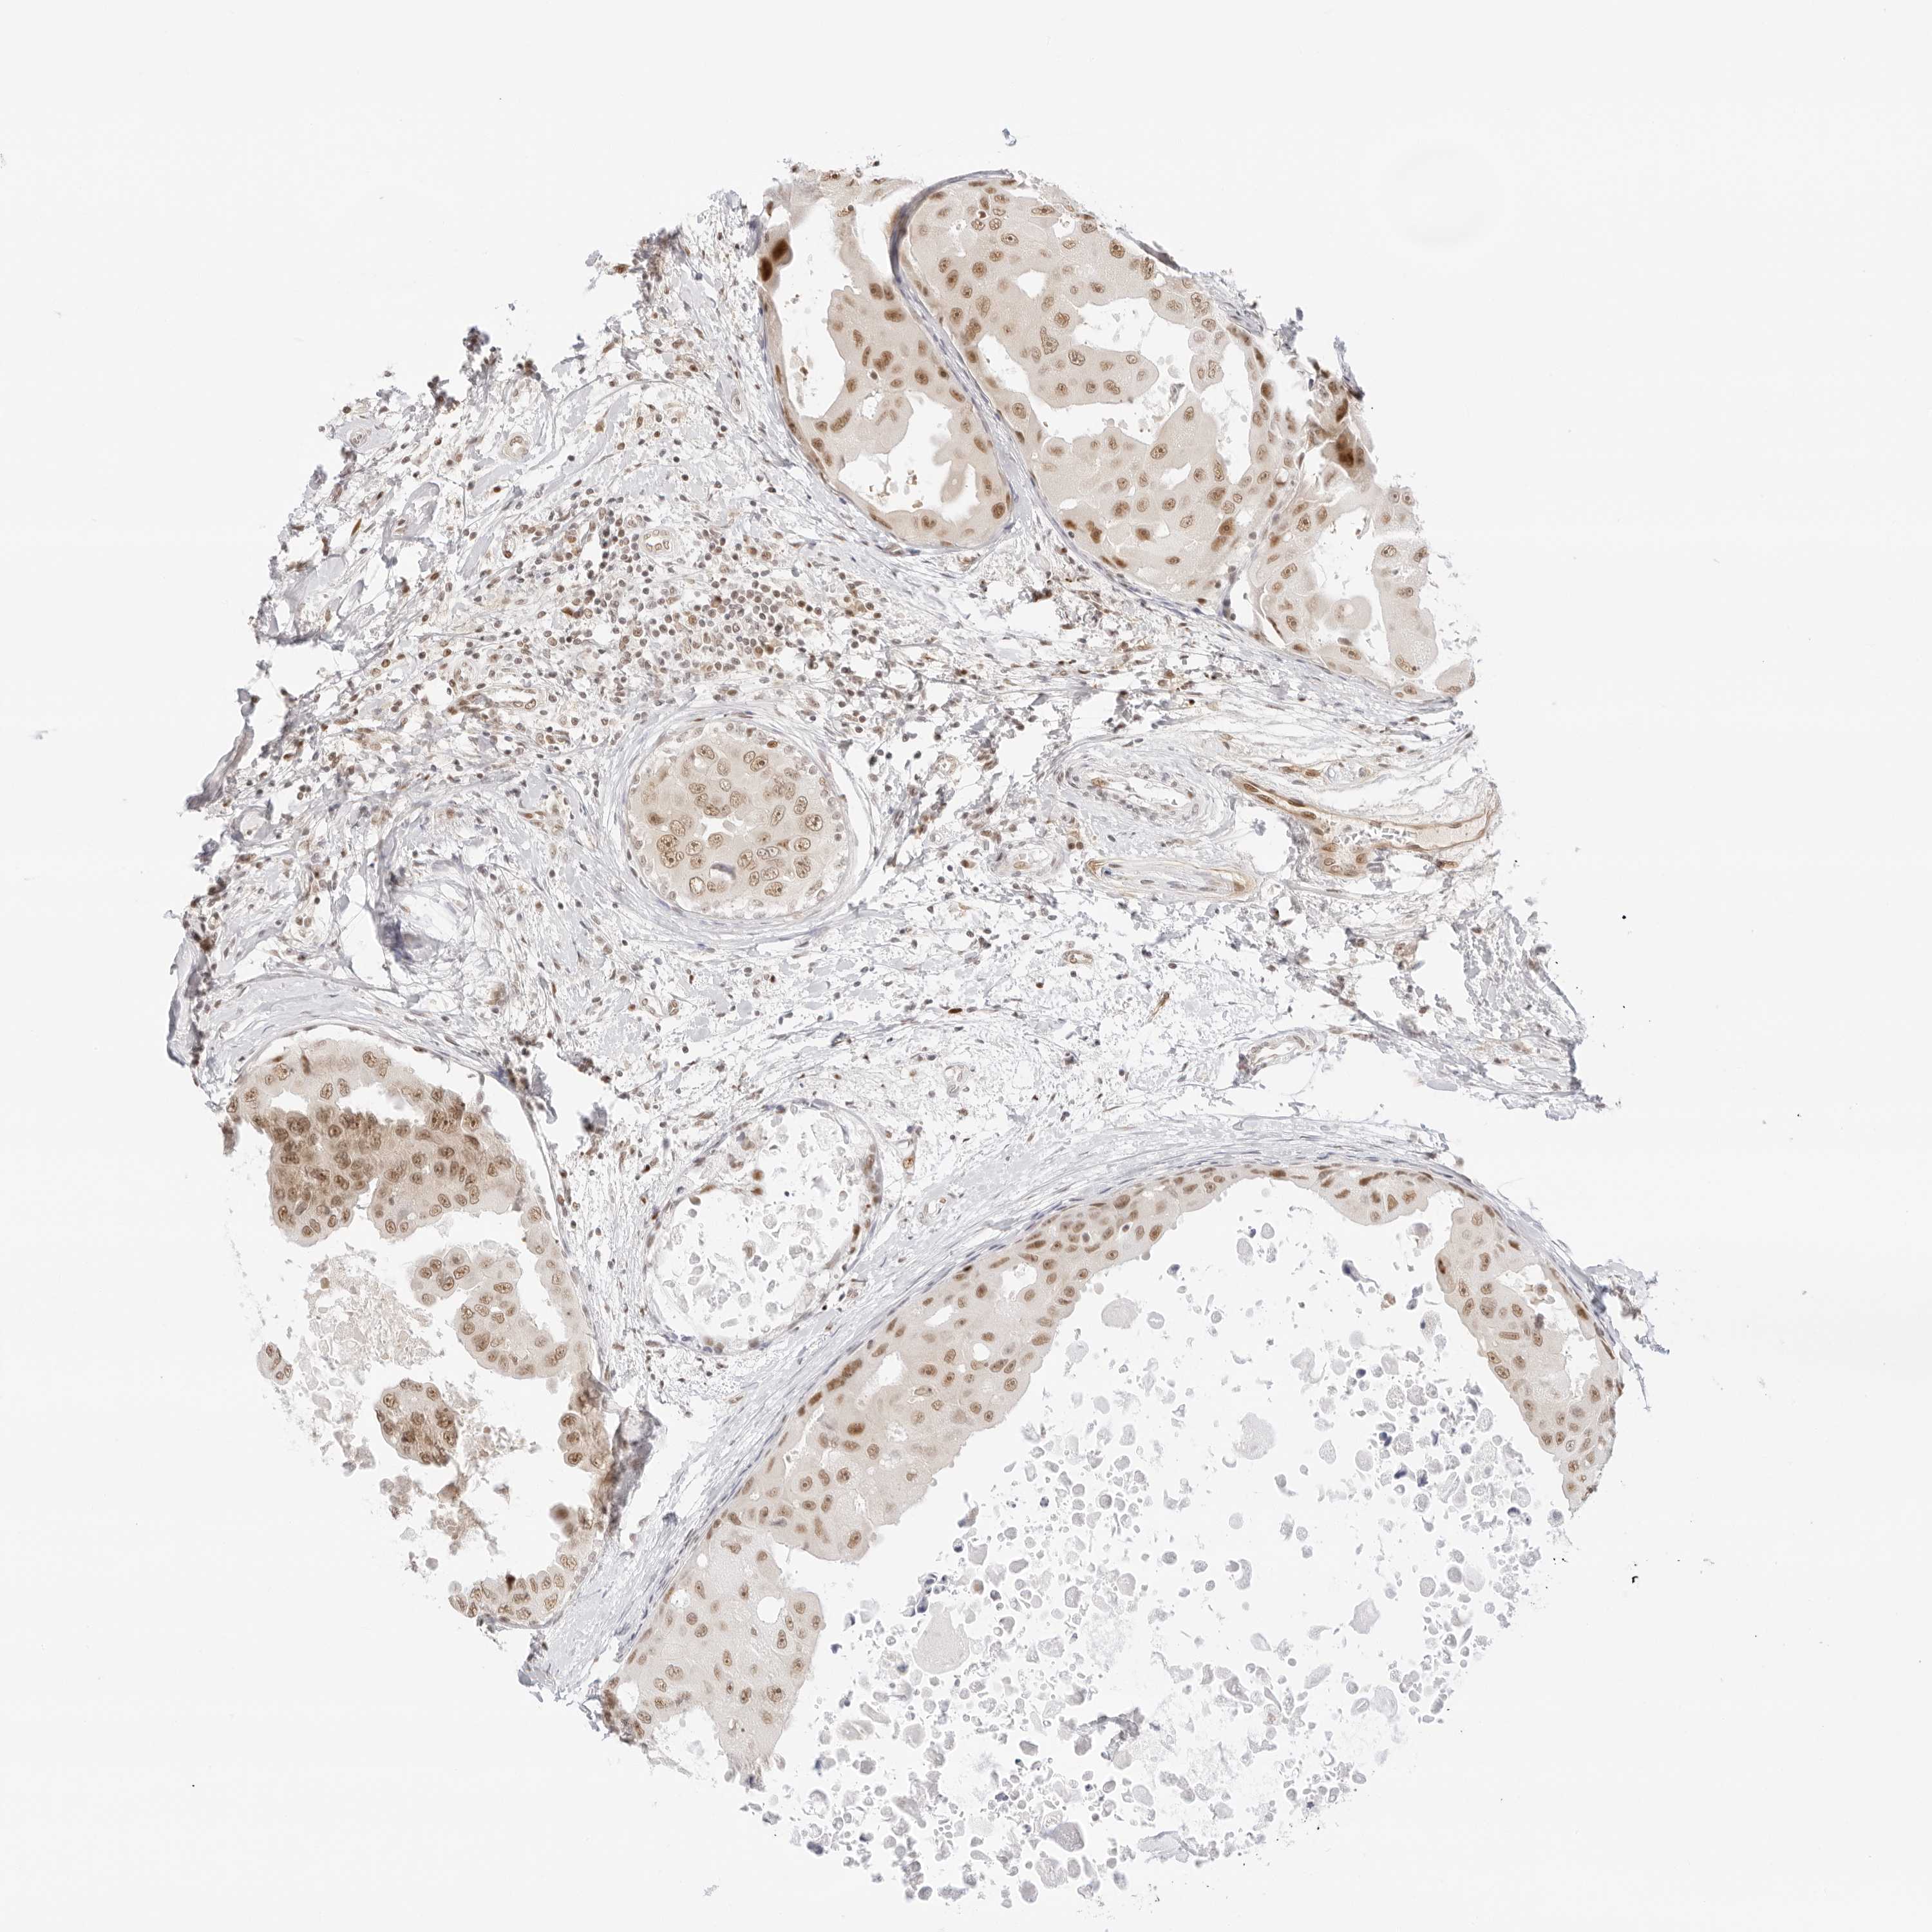

CANCER BREAST CANCER Show tissue menu

BRCA TCGA BRCA VALIDATION PROTEIN EXPRESSION